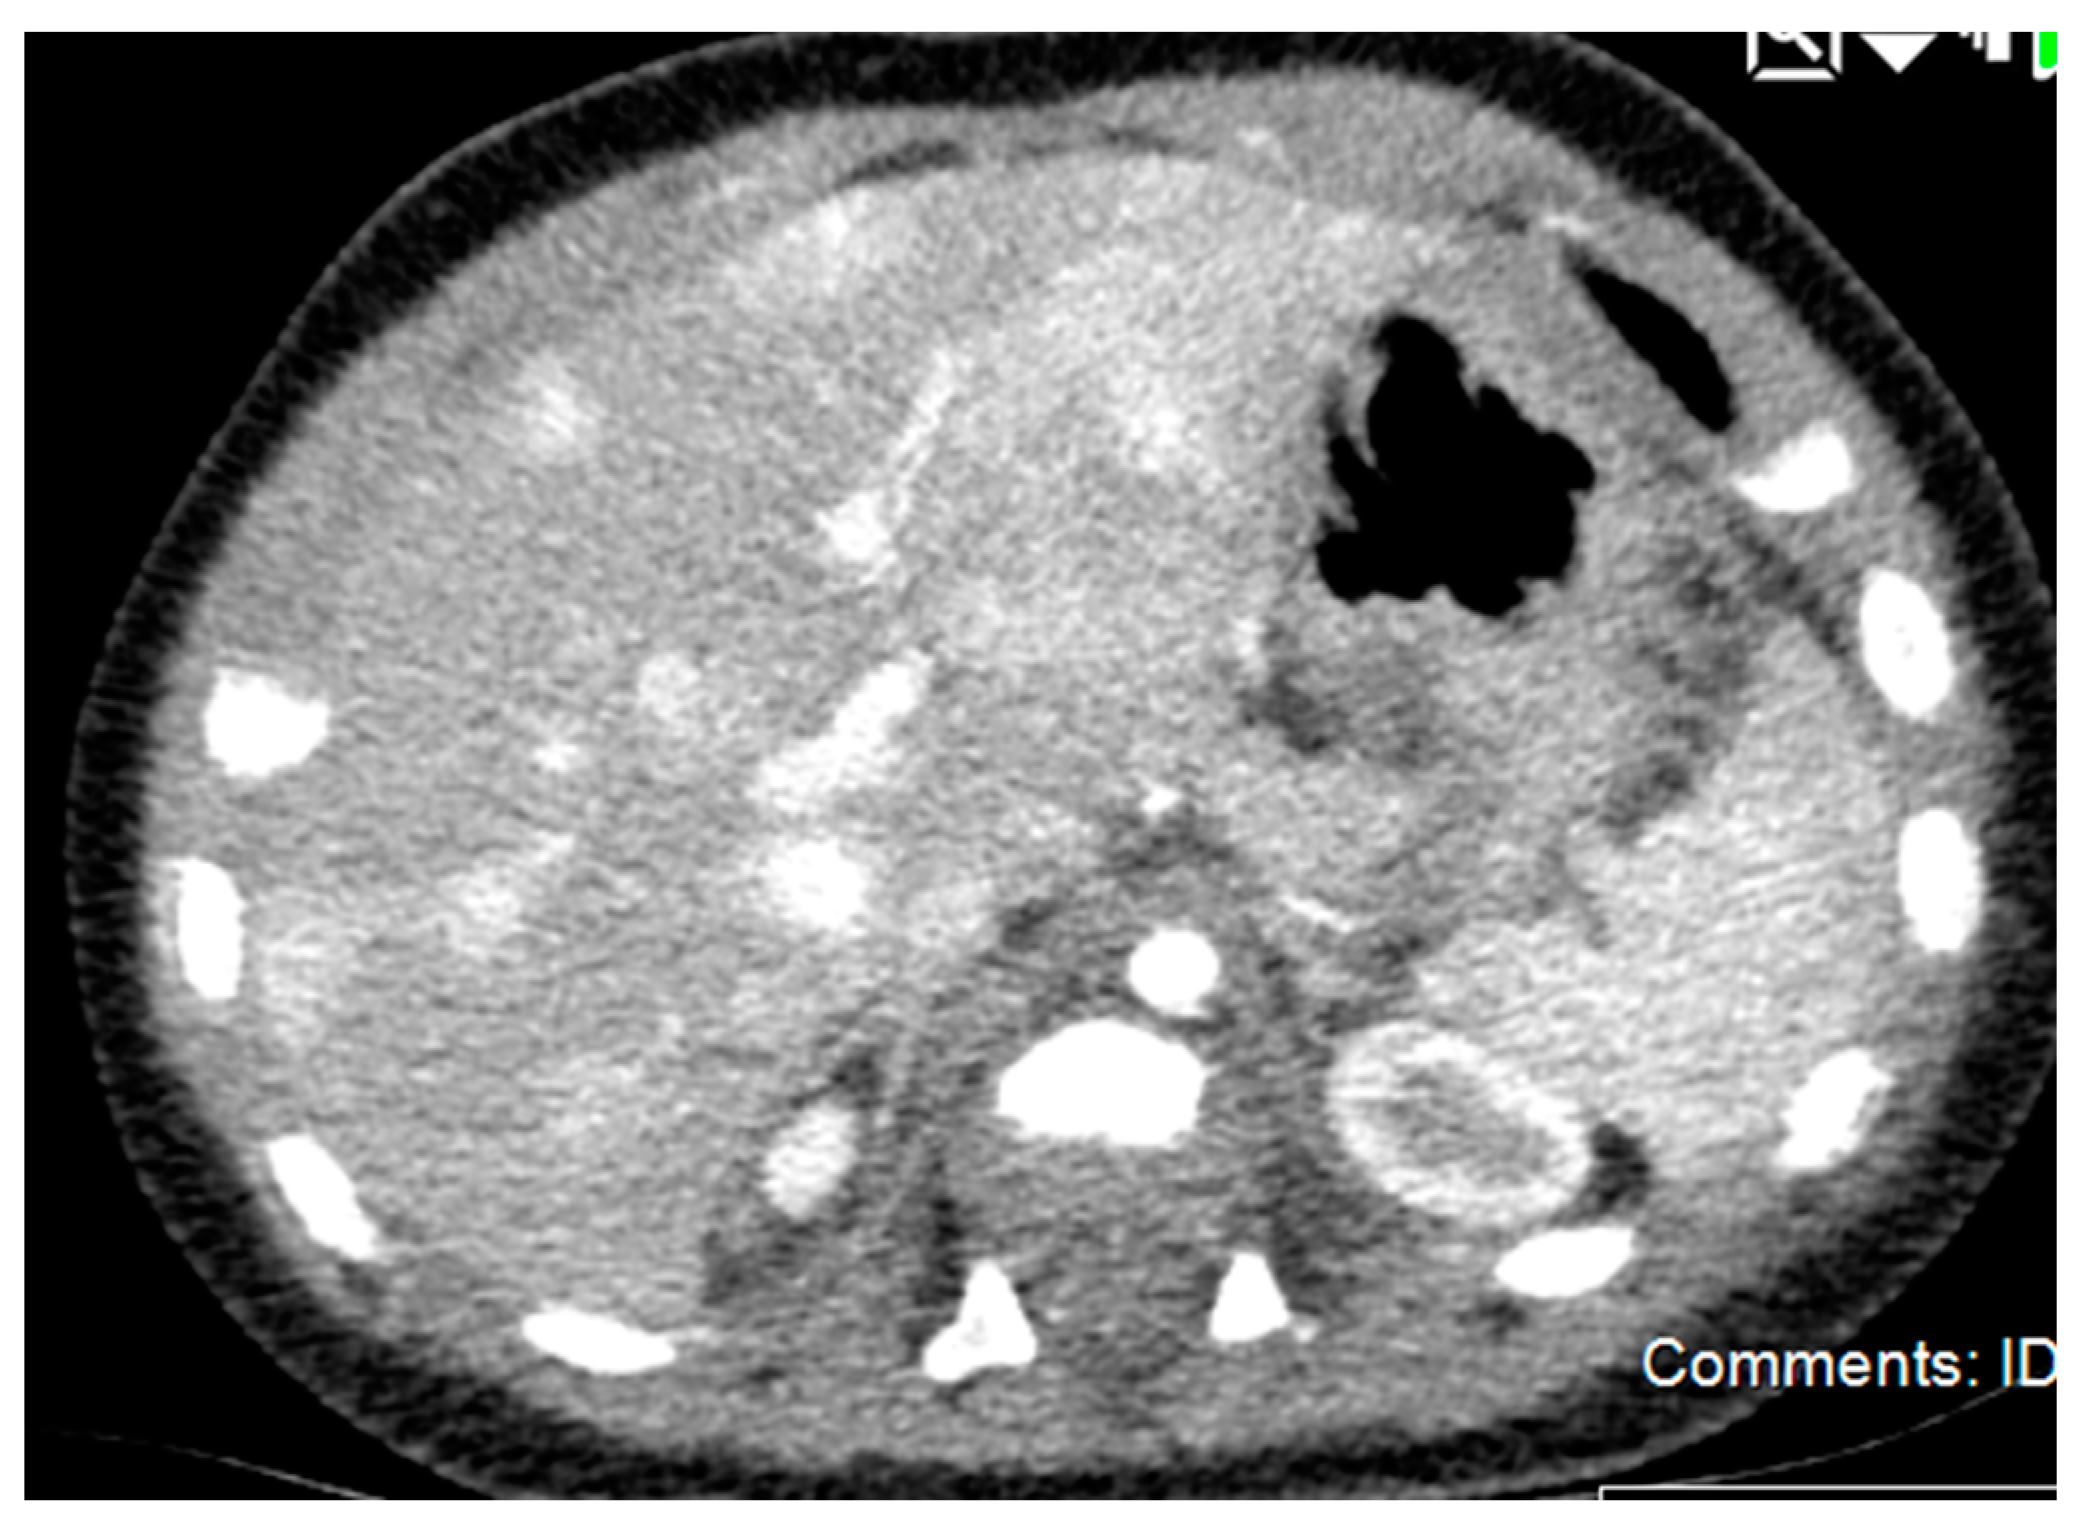

3.3.3. Diagnostic Imaging

5.2.4. Diagnostic Imaging